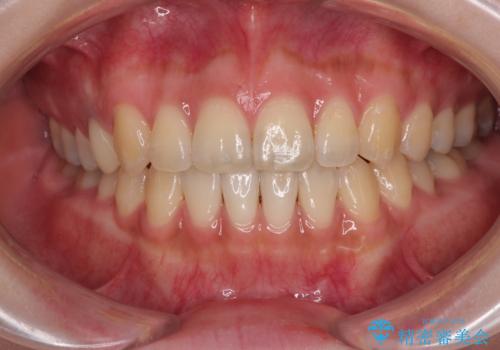

開咬をワイヤー装置で矯正治療

担当医 藤巻太一朗

オープンバイトをインビザラインで矯正治療